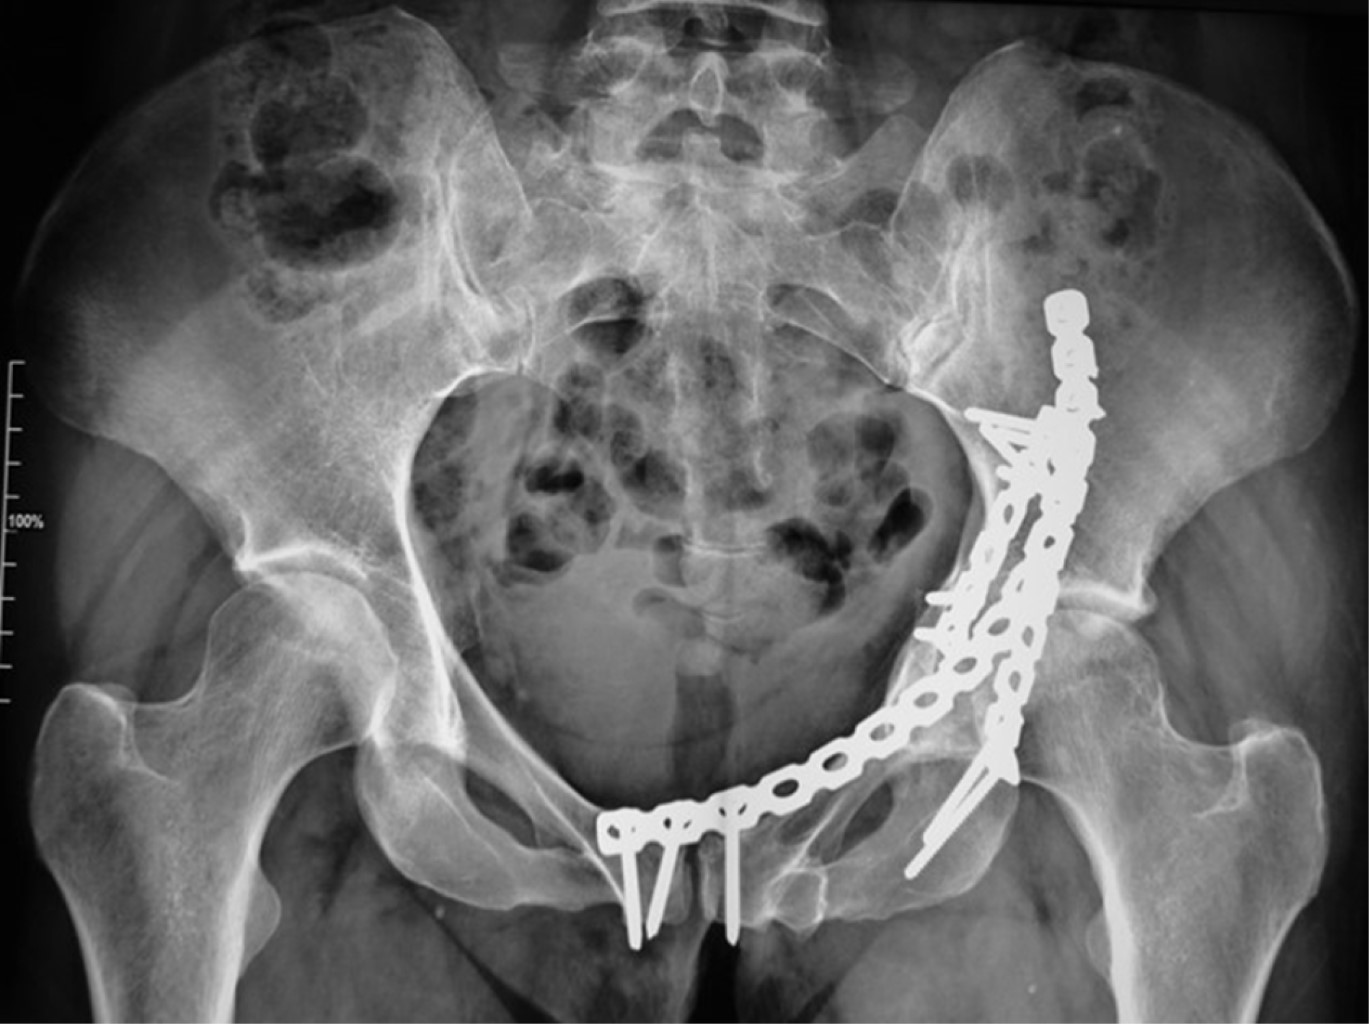

Una vez concluido el abordaje es posible realizar la reducción y osteosíntesis de las lesiones, bajo visión directa y con control fluoroscópico y posteriormente llevar a cabo el cierre.

Reparación del piso y del techo del canal inguinal: se sutura el tendón conjunto al remanente en el reborde pélvico con suturas preferentemente no absorbibles, posteriormente se repara el techo del canal afrontando los bordes del oblicuo externo previamente referidas (Figuras 7 y 8). La piel se cierra con grapas o suturas subdérmicas y se cubren con parches convencionales (Figura 9). El resultado radiográfico se muestra en la Figura 10.

Figura 10